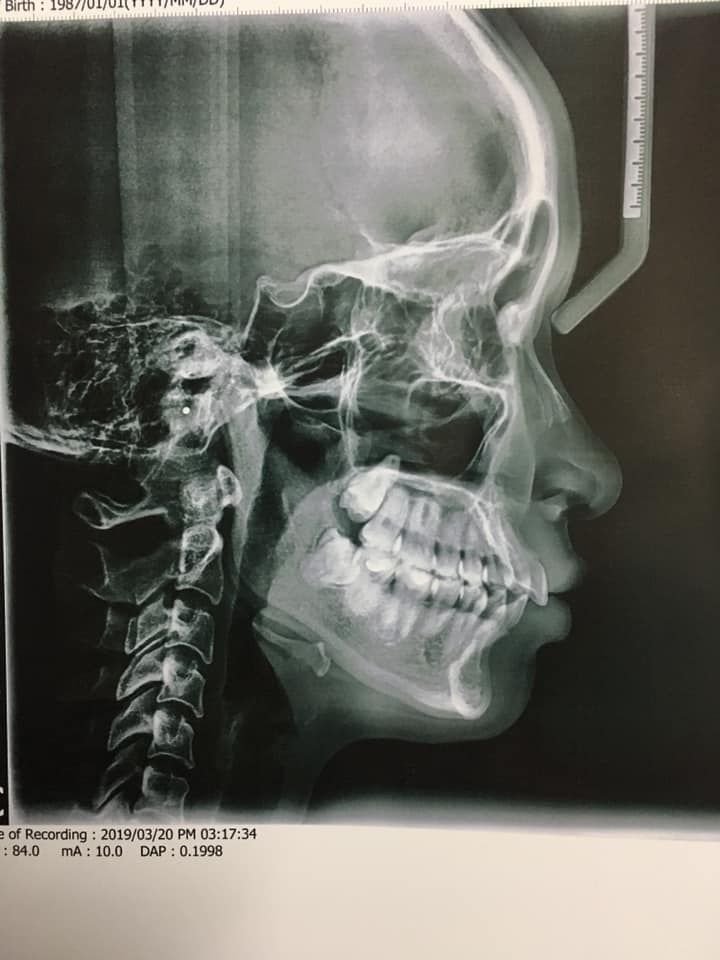

Em có 2 răng cửa thưa và chìa ra ngoài thế kia, hàm dưới hơi chìa 1 tí; khớp cắn ok nhưng Thái dương bị hóp sẵn ạ. Em đi khám bsi tư vấn 2 phương án: 1. Là nhổ 4r hàm nhỏ lấy khoảng kéo, 4 răng số 8 thì theo dõi nhổ sau; thì có thể mặt nghiêng niềng xong sẽ đẹp hơn, cằm Vline hơn. Nhưng em gầy lắm, 42 kg, cơ địa cực khó tăng cân. Thái dương lại hóp sẵn nên e sợ nhổ răng sẽ bị hóp nặng thêm lại như cái hình xương chéo người ta sơn ngoài cột điện, sợ mặt sẽ không đẹp dù răng có đẹp lên. 2. Nhổ ngay 4 răng số 8, và cắt kẽ, kết hợp chỉnh cung răng, đóng khe thưa, thì chỉ giảm hô được tầm 30% nhưng vì mặt nghiêng không hô mà chỉ cười nghiêng thì chìa ra thôi, cho nên 30% vẫn chấp nhận được. Tuy nhiên, không biết xong thì sẽ thành thế nào. Mong các bác sĩ tư vấn thêm ạ